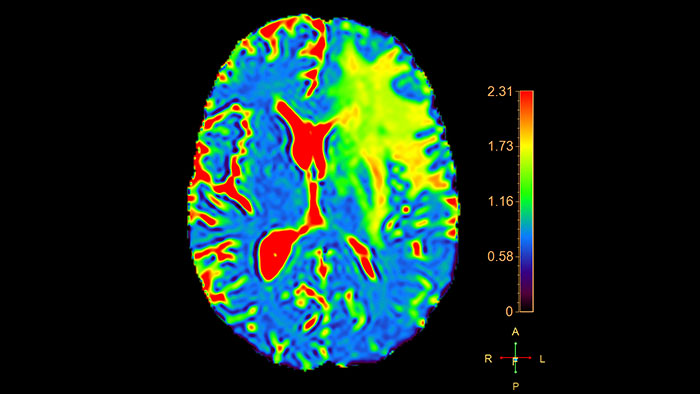

Determine areas of reduced cerebral blood flow as compared to the contralateral hemisphere

Generates qualitative and quantitative information about changes in image intensity over time. The application calculates and displays quantitative color maps of cerebral blood flow (CBF), cerebral blood volume (CBV), mean transit time (MTT) and time-to-peak (TTP), and provides summary maps which may help physicians in determining areas of reduced cerebral blood flow compared to the contra lateral hemisphere.